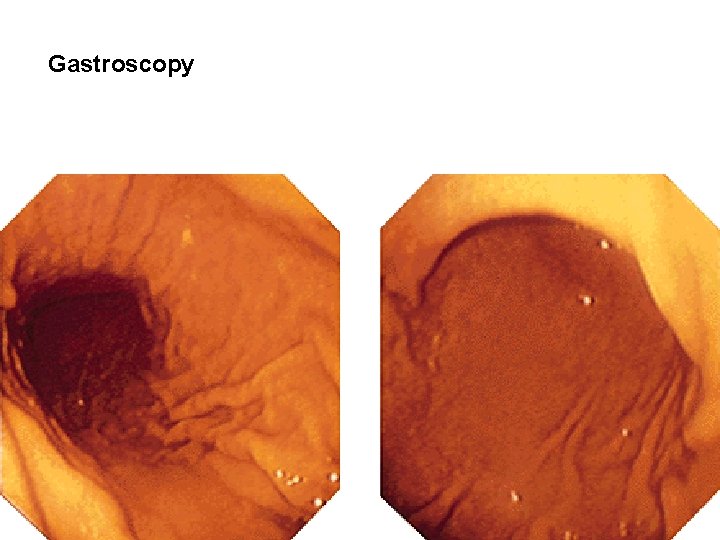

Gastroscopy